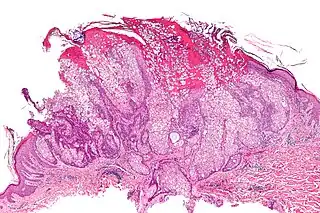

Adenoma sebáceo

Un adenoma sebáceo, es un tipo de adenoma, enfermedad cutánea que consiste en un tumor de crecimiento lento, habitualmente una pápula o nódulo de color rosa, carne o amarillo.[1]: 662 [2]

Los adenomas sebáceos aislados no revisten gravedad; sin embargo pueden estar asociados con el síndrome de Muir-Torre, una enfermedad genética que predispone al cáncer.[3]

Puede estar asociada con la esclerosis tuberosa. El término «adenoma sebáceo» es en realidad una denominación errónea.